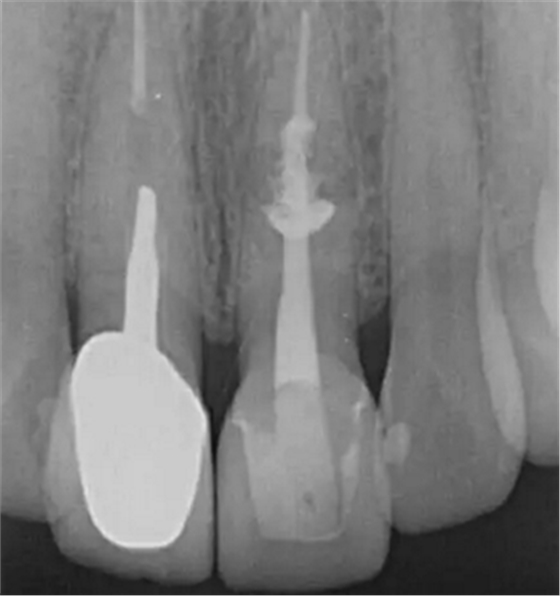

診斷:左上中切牙牙根內(nèi)吸收。治療計劃:左上中切牙根管治療,全冠修復。 治療過程:患者知情同意。使用含1/100,000腎上腺素的4%鹽酸阿替卡因(碧蘭麻,艾龍)局部浸潤麻醉,橡皮障隔濕。去腐未盡露髓,露髓孔出血多。開髓,使用10#不銹鋼K銼(MANI,日本)探查根管,根管中段有鈣化物阻擋,不能達到牙根全長(圖3A)。在顯微鏡下(Leica M400E,萊卡, 德國) 使用超聲尖(E1根管治療超聲尖,啄木鳥公司,中國)通開,采用根管長度測量儀(Root ZX, Morita公司,日本)加診斷絲片法(圖1B)測量根管長22 mm。使用控制扭矩馬達(X-smart,登士柏)和鎳鈦旋轉器械(Hero 642, Micromega)根管預備,根管預備過程中使用5.25%次氯酸鈉溶液沖洗。 根備完成后使用超聲蕩洗根管,5.25%次氯酸鈉溶液3 分鐘, 17% EDTA溶液1分鐘。干燥根管,使用螺旋充填器根管內(nèi)封氫氧化鈣糊,氧化鋅丁香油水門汀暫封。1周后患者復診,患者述無術后不適,檢查暫封完好,無叩痛,不松,牙齦無紅腫瘺管。使用橡皮障隔濕,去除暫封物,超聲蕩洗根管,5.25%次氯酸鈉溶液3 分鐘, 17% EDTA溶液1分鐘。干燥根管,牙膠尖(達雅鼎,中國)和必蘭根充糊劑(Cortisomol, 艾龍公司,法國)熱垂直加壓法根管充填。術后片顯示根充恰填,可見牙膠/糊劑被壓入鈣化物周圍和內(nèi)部縫隙內(nèi)

1月后復查無不適,行全瓷冠修復。8月2周后復查,患者無不適主訴,牙冠美觀,邊緣完好,患牙無叩痛,不松動,牙齦無紅腫瘺管, X線片示根周膜連續(xù),根尖周未見異常。建議患者避免用前牙撕咬食物,定期復查。 討論: 臨床上,由于牙根內(nèi)吸收和牙根外吸收的治療方法和預后不同,常需要對兩者進行鑒別診斷。過去通常采用偏移投照的方法鑒別兩者。在偏移投照片上,外吸收病損和根管輪廓相對位置較正位片會發(fā)生變化,而內(nèi)吸收病損則不會[12]。